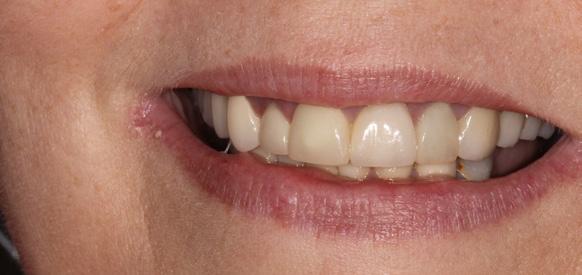

New Teeth In One Day, A state-of-the-art technique performed by Dr. Gregory

Do you ever catch yourself missing the familiar comfort of your own teeth? Frustrated with dentures that just don’t look or feel right? Or maybe, the mere thought of dentures has kept you from seeking treatment, fearing a life without the authenticity of your natural smile?

Welcome to Dr. Gregory’s “Teeth In One Day” solution – a transformative experience tailored just for you. This isn’t about just replacing teeth; it’s about reviving the confidence of your natural smile.

Imagine walking into Dr. Gregory’s cozy office, where you’re gently sedated for a worry-free procedure. Once you’re comfortably at ease, we replace any existing teeth with 4 to 6 state-of-the-art dental implants, precisely set into your jawbone. But here’s where the magic truly happens: a set of teeth, custom-

crafted uniquely for you, is secured onto these implants. This isn’t a temporary fix. These teeth will not only look, feel, and function like your natural teeth, but they’ll also stay with you, day in and day out – no nightly removals, no adjustments. Simply a new, permanent smile that’s unmistakably yours.

Why choose Dr. Gregory’s Teeth In One Day?

Commitment Beyond Procedures: We provide a lifetime of follow up care and personal accountability for our work. We won’t refer you out of our practice after your surgery is complete. We see you at least once a year to check our work and evaluate the health, function, and esthetic of your implants and your new teeth. You become part of our patient family.

Double the Care, Double the Quality: We provide you with two full sets of new teeth. Other practices frequently offer only one set of all-plastic (acrylic) teeth the day of surgery. We believe it is not acceptable to deliver an allplastic set of teeth as a final solution (plastic is porous and grows bacteria and fungus, is rough and difficult to clean). We provide an additional final set of teeth made of titanium with esthetic overlay or made of zirconia (ceramic). These materials are appropriate to protect the implants from infection and to provide a durable chewing solution and a beautiful long term result.

Unwavering Quality Standards: Your smile deserves the best. And we make no compromises there. We use quality implants and authentic implant parts. Dental implants are made by various manufacturers and are not all equal in quality or research support. Implants backed by years of research cost ten times what “knock off” implants can cost. Authentic parts that are fabricated to fit those implants are also more costly. We believe it’s absolutely worth the cost to have quality implants and implant parts used during surgery in an effort to minimize implant failures.

Tailored Just for You: No two smiles are the same, and neither should be the approach to care for them. We provide a customized surgery strategy for every patient. There is no one surgical plan that fits every patient. Every patient has a different dental history and a different personal story. There are many treatment options and we feel proud to offer a wide variety of techniques. We listen to our patients and help them arrive at a plan that makes sense for their dental condition, their emotional needs, and their financial possibilities.

Say goodbye to the inconveniences of conventional dentures and embrace a renewed, authentic smile with Dr. Gregor where you’re not just another patient; you’re family.

We offer comprehensive family dentistry and specialist services under one roof including preventive family dental cleanings, fillings, crowns, veneers, oral surgery, adult orthodontics, and periodontics. We also offer in-house dental insurance and work with employer insurance plans. We have a variety of financing options available.

Before & After Before & After